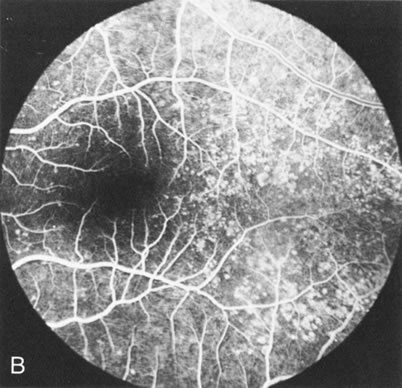

Fundus albipunctatus typically shows multiple, small white dots, which are deep in the retina, regular, and monotonous in their similar size, shape, and color and which involve the entire posterior pole into the equator while sparing the macula (Fig. 3A). These multiple dots are not apparent on FA. There may be a mottling of the background choroidal fluorescence and small areas of irregular transmission hyperfluorescence (especially surrounding the macula), but neither of these findings corresponds to the observed white dots8,9 (Fig. 3B).

Fig. 3. Fundus albipunctatus. The few small transmission defects on angiography (A) do not correspond to the multiple small white dots that are characteristic of this disease (B).